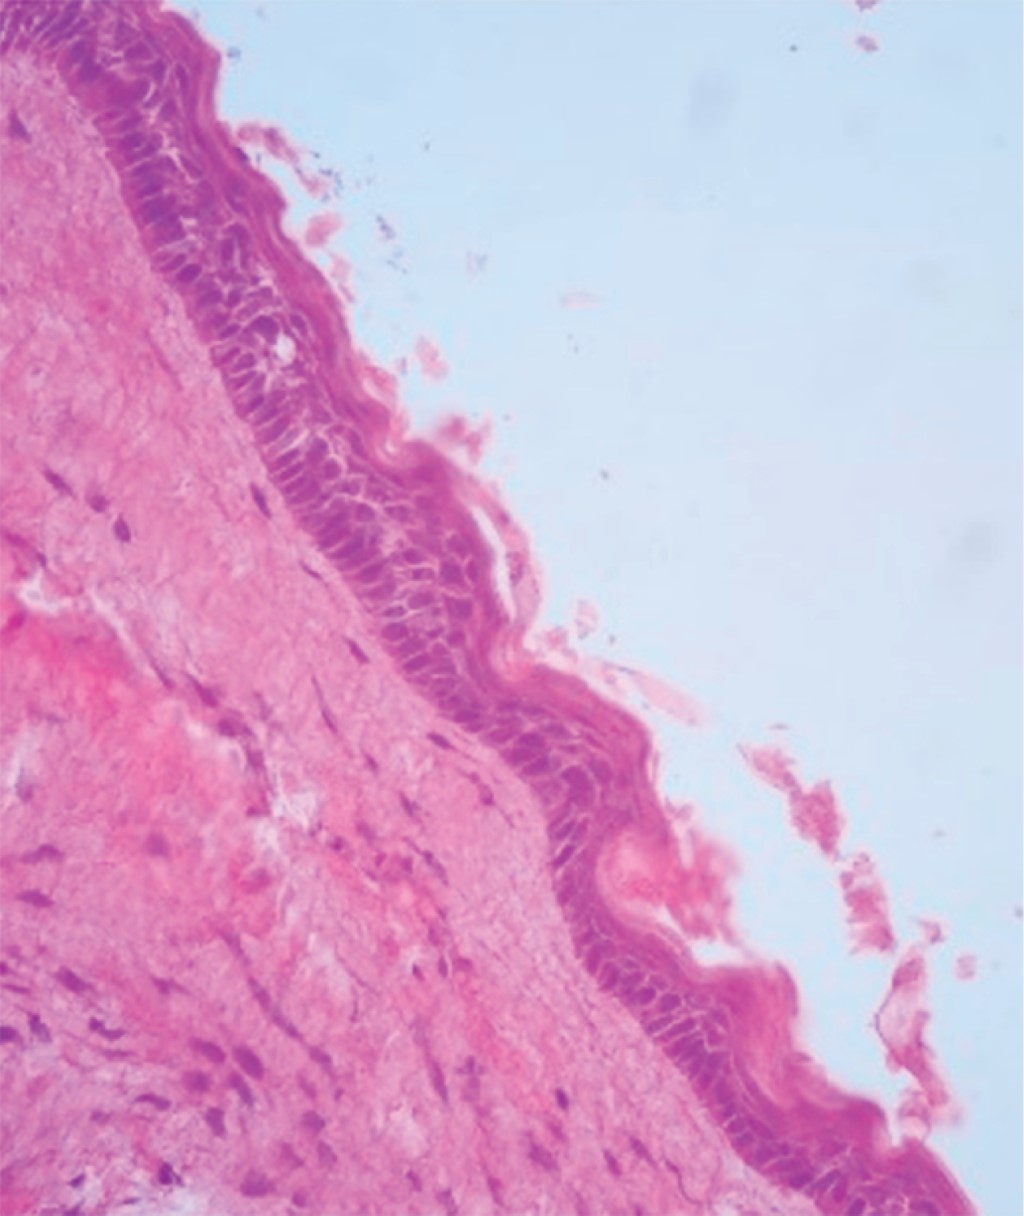

Al microscopio se observa quiste odontogénico delineado por epitelio plano estratificado paraqueratinizado. La superficie epitelial se observa corrugada y la basal se observa en empalizada. Pared de tejido conectivo fibroso. Focos discretos de inflamación crónica y áreas extensas de hemorragia reciente. Presencia de trabéculas óseas maduras de aspecto normal. No hay evidencia de malignidad en el tejido estudiado. Se obtuvo como diagnóstico histopatológico queratoquiste odontogénico (Figura 4).

Figura 4